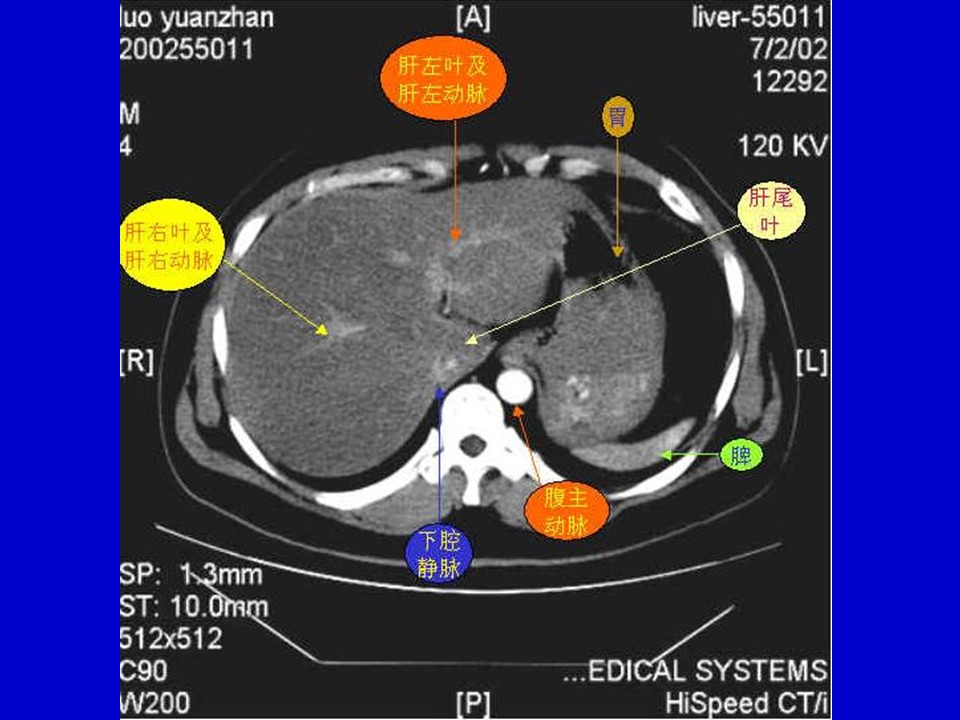

“肝脏的分段与血管走行PPT” 的相关文章